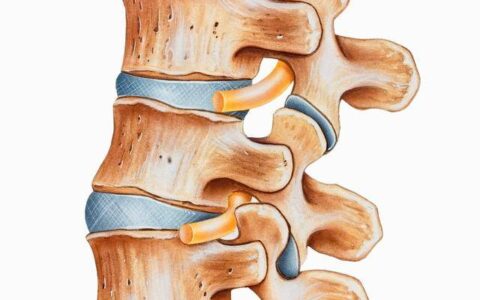

该方法是在CT引导下,经微创介入方式经皮穿刺切除部分椎间盘,将胶原蛋白水解酶注入病变的椎间盘突出物内或其周围,依靠胶原酶分解胶原蛋白的药理作用来溶解胶原组织,使突出物减小或消失,以缓解或消除其对神经组织的压迫,并可减轻或消除神经根的炎性反应,从而使病人的临床症状得到改善。

微创介入经皮椎间盘切吸术加胶原酶溶解术以创伤小、治疗费用低、远期疗效好、可重复性强等优点,受到越来越多患者的喜爱。对血管和其他组织没有损伤,实现了不开刀微创治疗的优势,更是充分体现了微创介入治疗的学科优势。

具有数十年微创介入治疗颈椎、腰椎间盘突出等疾病经验的杨浦区中医医院介入科周沛林主任,根据周阿婆严重的腰椎间盘突出,设计制定了个性化的治疗方案,将通常需要单独进行的五种微创术:造影、切除、吸引、消融、阻滞融为一体,进行复合式手术,确保了疗效,缩短了治疗周期,减少了创伤,减轻了痛苦,节省了费用,恢复快。